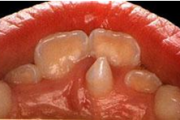

Hamba atritsioon